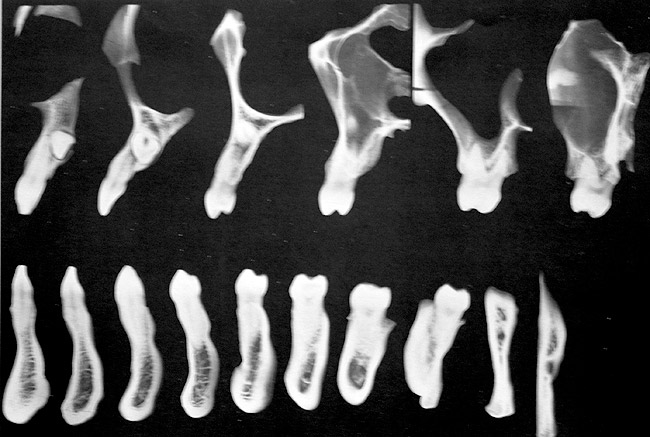

Another concern for loading of dental implants is implant alignment. When placing implants for the edentulous patient and an overlay or hybrid restoration is planned, the implants should then be placed as parallel as possible and slightly lingual to the actual tooth position. This allows establishment of normal contours of the prostheses and space for placement of the prosthetic teeth. Implants should not be placed in the central incisor region for a maxillary overlay prosthesis because this will compromise palatal contours, thereby affecting speech and tongue function. If, however, implants are planned for the partially edentulous patient and the replacement is for a natural tooth or teeth, then implants should be placed more in line with the long axis of the natural root. Teeth are designed to better handle the multitude of directional loads encountered during mastication when properly aligned on their bony base. Implants placed more in line with natural tooth roots that are properly positioned on their bony base may allow implants to better endure the various functional loads while promoting the continual physiologic bone remodeling necessary for long-term implant survival (Figure 6 and Figure 7). Depending on the type of anticipated function and the presence or signs of parafunctional habits, use of a maxillary biteplane/nightguard may be indicated (Figure 8). This can reduce the possibility of lateral loads, which have a detrimental effect on the dental implant(s). The biteplane is adjusted in centric relation with simultaneous occlusal contacts and shallow anterior guidance.

Figure 6  Tomograms showing natural teeth alignments on their bony bases (Wheeler R. Dental Anatomy, Physiology and Occlusion. 5th ed. Philadelphia, PA: WB Saunders; 1974:364).

Figure 6

Figure 7  Implants placed more in alignment with natural tooth roots.

Figure 7